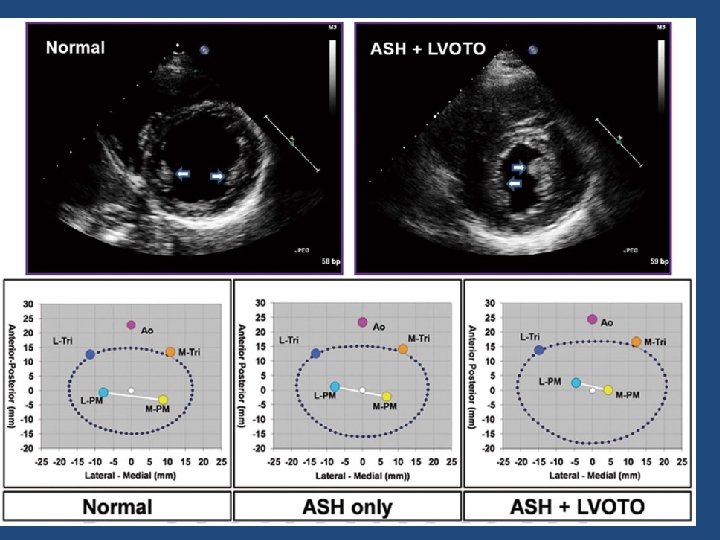

Explanations for the SAM of the mitral valve 1. Mitral valve is drawn toward the septum because of the lower pressure that occurs as blood is ejected at high velocity through a narrowed outflow tract (Venturi effect) 2. Mitral valve is pulled against the septum by contraction of the papillary muscles, which occurs because of the valve's abnormal location and septal hypertrophy altering the orientation of the papillary muscles 3. Hydrodynamic “drag” or the “pushing” force of flow

Patterns of systolic anterior motion of the mitral valve in hypertrophic cardiomyopathy: assessment by twodimensional echocardiography. –maron et al • In 36 patients (58%), both the anterior and posterior mitral leaflets appeared to participate in SAM. • In 19 patients (31%), SAM was produced selectively by the posterior mitral leaflet. • In only 6 patients (10%) was the anterior leaflet alone responsible for SAM. • In 51 patients (82%), only the distal portion of the anterior or posterior mitral leaflet approached the septum in systole.